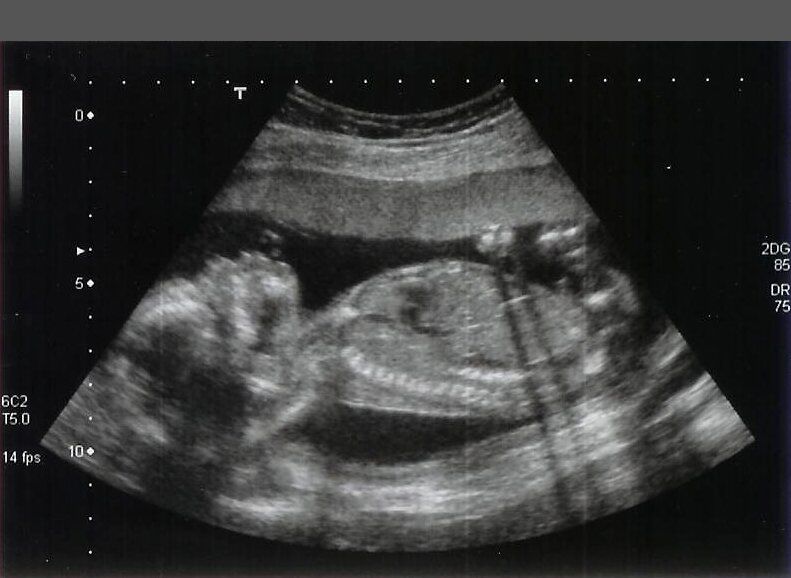

20 weken zwangerschap

-Gefeliciteerd, je bent op de helft van je zwangerschap! Nog ongeveer 20 weken te gaan tot je kleine wondertje er is. Het geslacht is nu eigenlijk altijd goed zichtbaar met behulp van een echo. Heb je nog geen pret-echo gedaan, dan krijg je (als je dit wilt) het geslacht waarschijnlijk te horen tijdens de 20-wekenecho.

Je baby meet al 25cm en weegt 300gram

Je baby gaat ook steeds meer vruchtwater slikken in deze periode. Dat is gelijk een goede oefening voor zijn spijsvertering. Hierdoor begint hij met het produceren van meconium. Dit zal ook de eerste ontlasting zijn van je baby. Meconium is meestal zwart en kleverig.(Tekst oorspronkelijk van baby24.nl)

dit is een mini mensje dat je laat verwijderen!